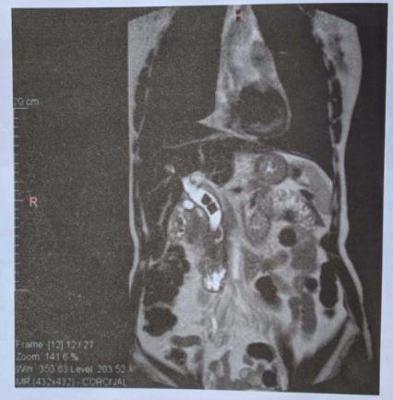

Mulher, 43 anos, foi internada em hospital terciário com quadro de dor abdominal de início súbito e icterícia há 2 dias. Ao exame físico: bom estado geral, fácies dolorosa, mucosas, mucosas descoradas e ictéricas 2+/4+. Frequência cardíaca: 108 bpm, frequência respiratória: 24 irpm. Abdome plano, tenso, difusamente doloroso e sem sinais de irritação peritoneal. Exames laboratoriais: hemoglobina: 13,7 g/dL; leucócitos: 8.756 (4% bastões e 96% neutrófilos); bilirrubina total: 6,62 mg/dl; bilirrubina direta: 5,2 mg/dl; fosfatase alcalina: 571 U/L; TGO: 52 U/L; TGP: 41 U/L; albumina: 3,8 g/dl; INR: 1,1; amilase: 862 U/L e lipase: 120 U/L. Na admissão, foi solicitado uma colangioressonância magnética. Qual a melhor conduta imediata?